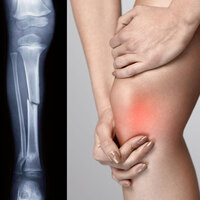

Samsun'da bir ortopedi uzmanı doktor tarafından yapılan ve dünyada bir benzeri olmayan "Ortopedi Robotu" ile kırıklar açık ameliyata gerek kalmadan tedavi edilebilecek.

İHA'nın haberine göre; 5 yıl önce zorlu bir kırık ameliyatından çıktıktan sonra aklına bir cihazla bu işlemin yapılabileceği fikri gelen Opr. Dr. Burak Tuna, mühendis arkadaşlarının yardımıyla 3 yıl süren çalışmalar sonucunda "Ortopedi Robotu" ismini verdiği bir cihaz yaptı. Kırılan kemikleri normalden daha kısa sürede yerine oturtan robot, hem zamandan tasarruf sağlıyor hem de kemikleri daha iyi bir şekilde yerine oturtabiliyor. Robota sabitlenen kırık kemik parçaları joistik yardımıyla uzaktan bir ekran vasıtasıyla yerine oturtulabiliyor. Uzaktan müdahale ve kısa sürede işlemin sona erdirilmesi sayesinde radyasyonun etkileri de en aza indirgeniyor. Deney hayvanları üzerinde oldukça başarılı sonuçlar veren Ortopedi Robotu, 6 ay içerisinde insanlar üzerinde denenmeye başlanacak. Ortopedi Robotu'nun patentini de alan Tuna, dünyada başka benzeri olmayan robotun insanlığa büyük fayda sağlayacağını belirtti.

Ortopedi Robotu'nun kırık ameliyatlarına büyük kolaylık sağlayacağını belirten Samsun Gazi Devlet Hastanesi Ortopedi Uzmanı Opr. Dr. Burak Tuna, "Kırık ameliyatlarında kırık uçlarını elle uç uca getiriyoruz. Bu her zaman istenilen şekilde olmayabiliyor. Bu güç gerektiren ve hassas bir işlem olduğu için insan gücü yeterli olmayabiliyor. Ayrıca bu işlem röntgen cihazı altında yapıldığından hem hasta hem de ameliyat ekibi uzun süreli radyasyona maruz kalabiliyor. Yaklaşık 5 yıl önce kırığı olan bir hastayı ameliyat ederken bu zorlukla karşılaştım. Ameliyattan çıktıktan sonra böyle bir proje aklıma geldi. Öyle bir robot olsun ki benim yerime geçsin; kırığın uçlarını hatasız, milimetrik ve kısa sürede bir araya getirsin. Bunu araştırdım ve dünyada böyle bir cihazın olmadığını gördüm. Bu konuyu mühendis arkadaşlarımla paylaştım. Daha sonra AR-GE çalışmalarına başladık. Ben robotun nasıl bir şey olması gerektiğini tarif ettim. Arkadaşlarımla birlikte 3 yıl süre içerisinde cihazın prototipini yaptık ve patentini aldık. İl Sağlık Müdürlüğümüz ile ilgili çalışmalarımız devam ediyor. İnşallah bu proje Türkiye ve halkımız için faydalı olacak ve bunu dünyaya ihraç edeceğiz. Deney hayvanları üzerinde denemelerimizi yaptık. Başarılı sonuçlar aldık. Son prosedürleri de tamamlayarak 6 ay içerisinde bu robotu insanlar üzerinde denemeye başlamayı hedefliyoruz" dedi.

Kapalı ameliyat yöntemi ile cihazın işlem yaptığını belirten Tuna, "Bu ameliyatlar kapalı veya açık yapıldığında 2 saat sürebilen ameliyatlar. Bu robotla ameliyat süresi 15 dakikaya iniyor. Sürenin azalması ve ameliyathanenin uzun süreli işgal edilmemesi açısından da önemli bir avantaj. Bu gibi durumlarda genel olarak açık ameliyatlar yapılıyor. Fakat bu robotun sayesinde kapalı ameliyatlara dönüleceğine inanıyorum. Ameliyat kapalı olduğu için de enfeksiyon riski de büyük oranda azalacak. Bu cihazın dünyada başka bir örneği yok. Amacımız bu ürünü devletimizin desteğiyle Türkiye'ye üretip dünyaya pazarlamak" diye konuştu.